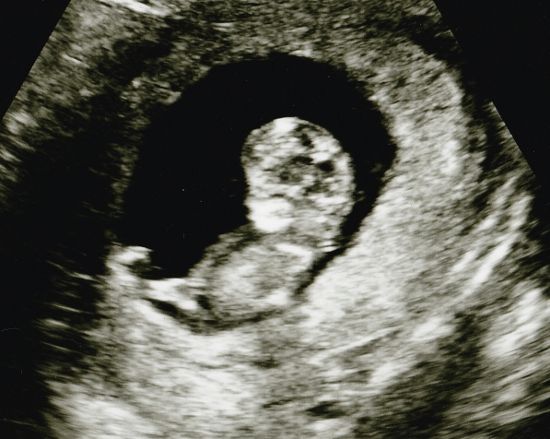

Siellä hän oli. ♥ Hyvinvoivan oloisenakin vielä, eikä mitään tavallisesta poikkeavaa tällä erää löydetty. Hiukan yllätyksenä itselleni tuli kuitenkin se, että pikkuinen oli jo juuri niskapoimumittauksiin sopivan kokoinen, sillä odotin ikää olevan ainakin reilun viikon vähemmän. Raskausviikkoja siis arvioitiin eilen mitatessa olevan 11+5 ja todennäköisimmäksi lasketuksi ajaksi saatiin 11.11.2015. Niskapoimun/turvotuksen mitaksi saatiin 0,84 mm, jonka todettiin olevan normaali. Toivottavasti jossain vaiheessa saatavat seulan tulokset ovat hyvät nekin.

Oli ihanaa nähdä, että siellähän se pieni jo hyvinkin ihmistä muistuttava otus oikeasti oli. Itsepäisen oloinen tapaus jo, joka alkuun villisti riehuttuaan päätti varsinaisen tutkimisen ajan koittaessa jämähtää tiukasti paikalleen köllöttämään, selkä kohti "kameraa". Vaadittiin hyvä tovi varsin ikäväntuntuista alavatsan tökkimistä ja täristelyä, kunnes pieni sentään lopulta suostui kääntyilemään hiukan parempaan asentoon ja tarvittavat profiilikuvat saatiin.